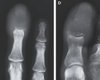

22.07.2025 12:12 Технологии и наука У 55-летнего мужчины отекли пальцы: кости в них полностью заменил собой рак